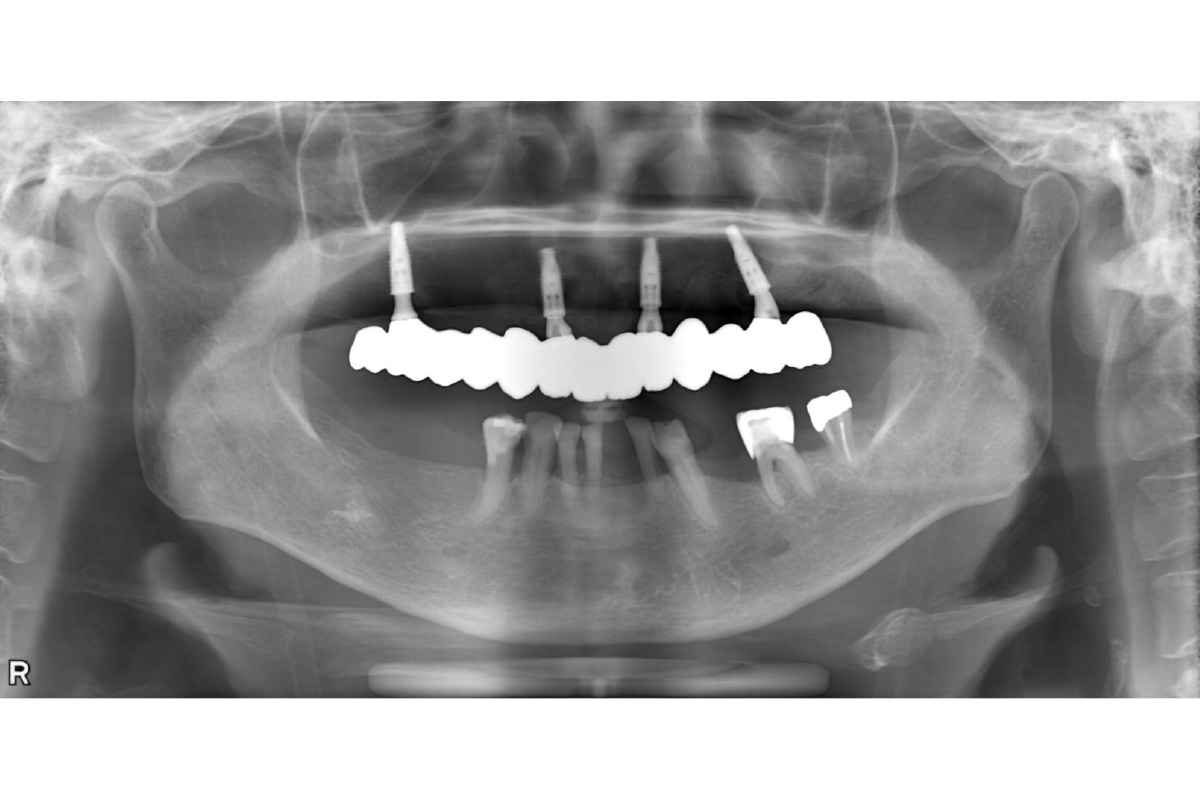

インプラント治療 オールオン4上顎の歯をキレイに治したい治療費を抑えたい 2026.03.11 上顎の歯をキレイに治したい。治療費を抑えたい。 治療前 治療後 治療前 インプラント(オールオン4) 治療後 担当医 小林 健一 先生 主訴 上顎の歯をキレイに治したい。治療費を抑えたい。 期間 費用 2,500,000円(治療時) 治療内容 仮歯 インプラント補綴(オールオン4) 静脈内鎮静法 治療に伴うリスク 外科処置を伴う 関連症例 インプラント治療審美歯科 前歯をインプラントで治したい。両隣の歯も揃えてキレイにしたい。 担当医 小林 健一 先生 主訴 前歯をインプラントで治したい。両隣の歯も揃えてキレイにしたい。 期間 4ヵ月 費用 899,800円(治療時) 治療内容 右上中切歯へのインプラント治療 (骨造成、結合組織移植) 両隣在歯のジルコニアクラウン 治療に伴うリスク 外科処置を伴う 2026-03-11 ジルコニアクラウン両隣の歯も揃えたい結合組織移植術骨造成 インプラント治療 左下の歯を入れ歯以外で治したい。前歯のブリッジはそのままで治したい。 担当医 小林 健一 先生 主訴 左下の歯を入れ歯以外で治したい。前歯のブリッジはそのままで治したい。 期間 5ヵ月 費用 566,500円(治療時) 治療内容 骨造成 結合組織移植術 インプラント治療 治療に伴うリスク 外科処置を伴う 2026-03-11 結合組織移植術骨造成 インプラント治療 下顎の入れ歯の安定が悪い。美味しい食事を取りたい。 担当医 小林 健一 先生 主訴 下顎の入れ歯の安定が悪い。美味しい食事を取りたい。 期間 5ヵ月 費用 2,457,400円(治療時) 治療内容 インプラント治療(フラップレス手術) 治療に伴うリスク 外科処置を伴う 2026-03-11 しっかり噛めるようになりたい入れ歯が合わない インプラント治療審美歯科 前歯の抜歯が必要となった。隣の歯も含めてキレイに治したい。 担当医 小林 健一 先生 主訴 前歯の抜歯が必要となった。 隣の歯も含めてキレイに治したい。 期間 6ヵ月 費用 1,179,200円(治療時) 治療内容 ジルコニアクラウン3本 インプラント治療2本 骨造成 治療に伴うリスク 外科処置を伴う 2026-03-12 ジルコニアクラウン前歯をキレイにしたい骨造成 インプラント治療 左下の奥歯を入れ歯以外で治したい 担当医 小林 健一 先生 主訴 左下の奥歯を入れ歯以外で治したい 期間 6ヵ月 費用 1,152,800円(治療時) 治療内容 抜歯・骨造成 インプラント治療 治療に伴うリスク 外科処置を伴う 2026-03-11 奥歯のインプラント骨造成 インプラント治療 前歯が折れた。抜歯はいいが、残りの歯を削らずにインプラントで治したい。 担当医 小林 健一 先生 主訴 前歯が折れた。抜歯はいいが、残りの歯を削らずにインプラントで治したい。 期間 5ヵ月 費用 686,400円(治療時) 治療内容 インプラント(抜歯即時埋入) 骨造成 カスタムアバットメント作成 治療に伴うリスク 外科処置を伴う 2026-03-11 歯が折れた骨造成 インプラント治療 抜歯となった。インプラントで治したい。 担当医 小林 健一 先生 主訴 抜歯となった。インプラントで治したい。 期間 4ヵ月 費用 455,950円(治療時) 治療内容 インプラント治療(抜歯即時埋入) 骨造成 治療に伴うリスク 外科処置を伴う 2026-03-11 抜歯即時インプラント骨造成 インプラント治療 左上の前歯が折れた。インプラントで治したい。 担当医 小林 健一 先生 主訴 左上の前歯が折れた。インプラントで治したい。 期間 4ヵ月 費用 628,650円(治療時) 治療内容 インプラント治療(抜歯即時埋入) 骨造成 結合組織移植術 治療に伴うリスク 外科処置を伴う 2026-03-23 前歯が折れた抜歯即時インプラント結合組織移植術骨造成